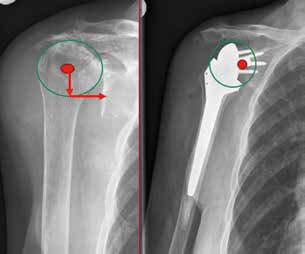

Für den Fall, dass nach adäquater Diagnostik keine Ursache für die Instabilität ermittelt werden kann, kann in Einzelfällen mit Hilfe eines Anbindungsschlauchs Stabilität erreicht werden 33 (Abb. 3). Anschließend ist nach Auffassung der Autoren die Immobilisation in einer Orthese für 3 Monate zu empfehlen.

Bei einer Instabilität gilt es, zunächst die oben dargestellten Faktoren zu evaluieren (Rotations-CT sowie ArmGanzaufnahmen im Vergleich zur Gegenseite). Finden sich hier Auffälligkeiten, sollte keine geschlossene Reposition, sondern eine operative Revision erfolgen. Lassen sich keine Auffälligkeiten ermitteln, kann eine geschlossene Reposition in etwa 50 % der Fälle erfolgreich sein. Hieran sollte sich für 6 Wochen eine Immobilisation – idealerweise in einem Abduktions-Brace – anschließen. Finden sich keine biomechanischen Auffälligkeiten im Bereich der Prothesengeometrie, kann in Einzelfällen mit einem Anbindungsschlauch eine Stabilisierung versucht werden. Danach empfehlen die Autoren bis zur narbigen Einheilung eine Brace-Anwendung für 3 Monate.